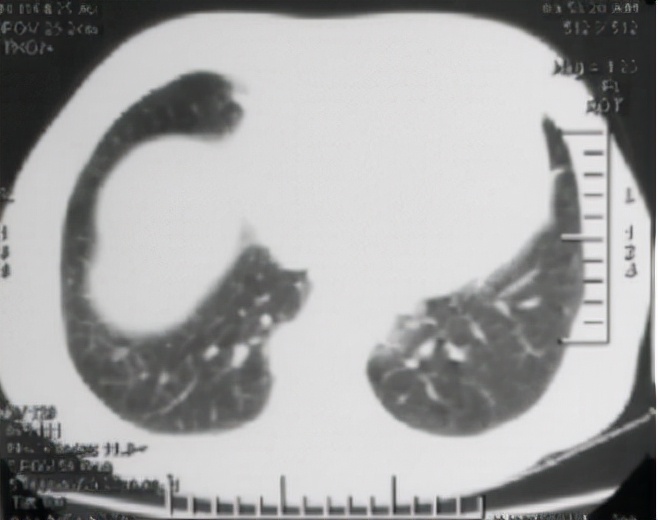

2021年11月30日,冯女士复查胸部 CT;

①左肺上叶下舌段少许陈旧性病灶;

②前片所示左肺下叶小结节未见显示,考虑炎性结节吸收 ( 见下图 ) 。

结节吸收,一般人可能从字面意思上不太明白,让我来告诉你——它的意思就是说, 结核结节缩小或者消失了,冯女士再也不用担惊受怕了。